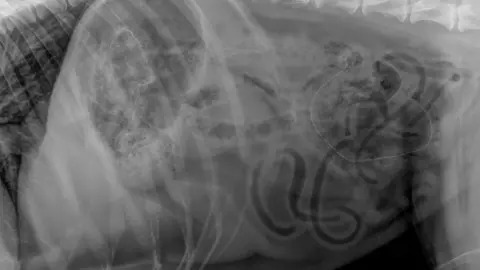

Vets NowThe pet was treated at an emergency pet hospital in Manchester, where an X-ray revealed the tinsel twisted up inside his abdomen.